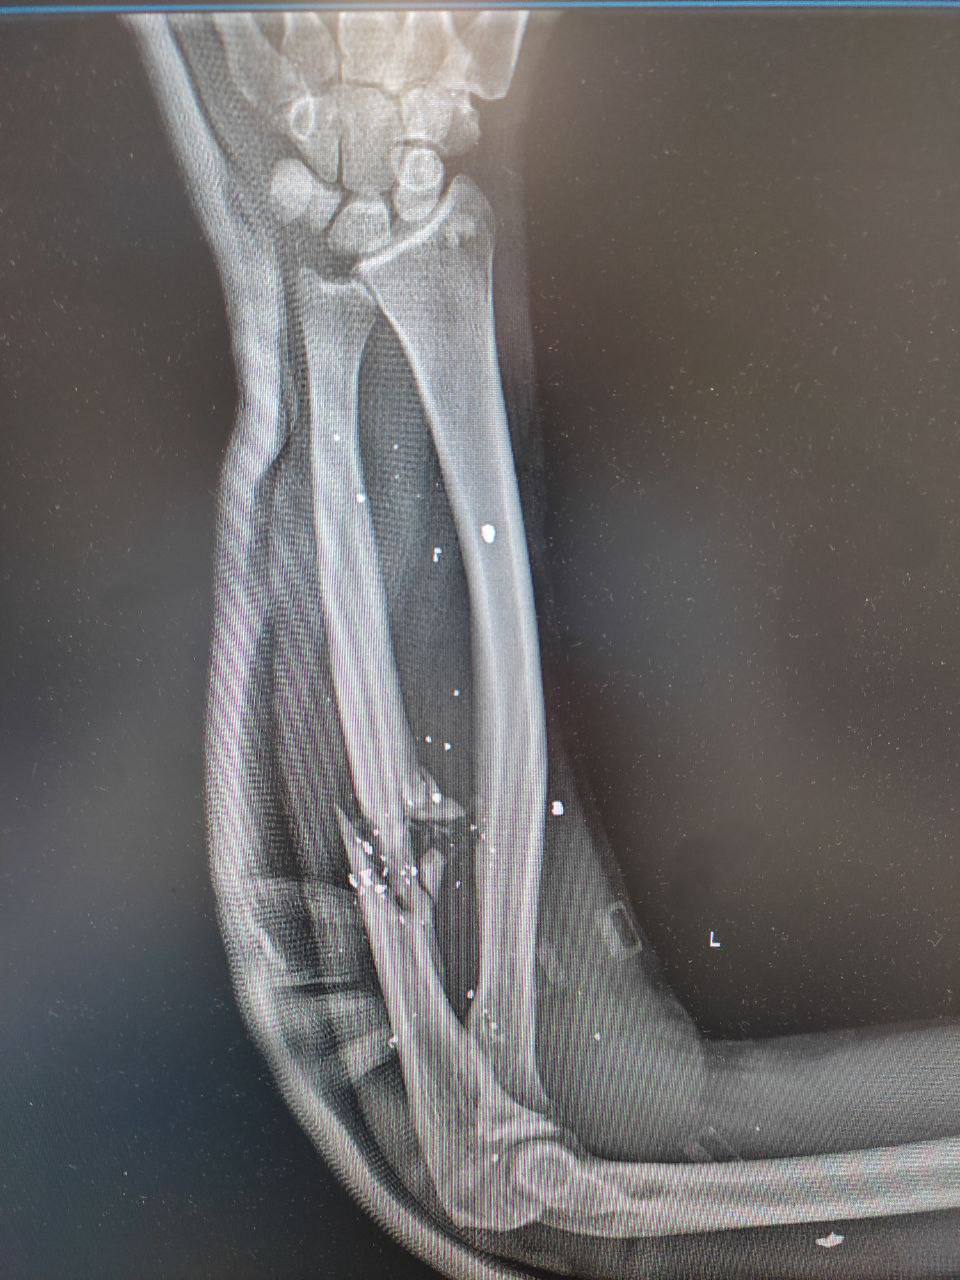

- Можна піти на МРТ, щоб витягти всі уламки за один раз – магнітом (сміється. – О.М.). На жаль, цього неможливо зробити. Вони вже на все життя. Якщо подивитися мій рентген – там усе біле. У мене ось не вистачало три сантиметри кістки (показує ліву руку, яка вся в шрамах. – О.М.) – вирвало.

- Ні. Сухий закон. Я завжди їм кажу: "Ви – честь українського народу!". Якщо військовий дозволяє собі перебувати десь у стані алкогольного сп’яніння, так його й сприйматимуть. А я хочу, щоб в Україні було таке ставлення до військовослужбовців: це люди, які віддали своє здоров’я, життя за те, щоб українці жили далі на своїй землі. Це приклад! Тому й поведінка має бути відповідною, щоб не відбувалося знецінення того, що ми робимо. Для мене важливо, що про нас думають. Я віддаю війні всього себе. У мене двоє дітей. Я зараз на третій групі інвалідності. В мені – мінімум 130 уламків (це ті, які можна порахувати)...